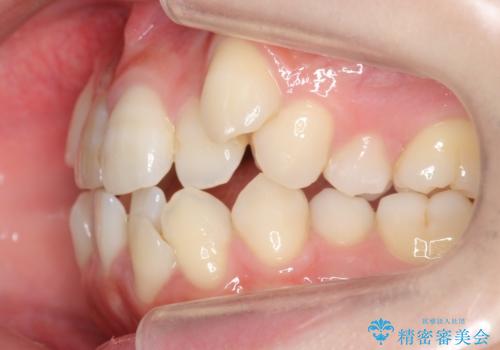

八重歯と、前歯のやや開咬の症状もあり難易度としては中等度でした。

上下左右の小臼歯を抜歯し、ワイヤー矯正を行いました。

犬歯のコントロールが難しく、矯正用ミニスクリューを併用しました。

奥歯の歯の間が狭く、ミニスクリューを入れるのも難しい症例でした。